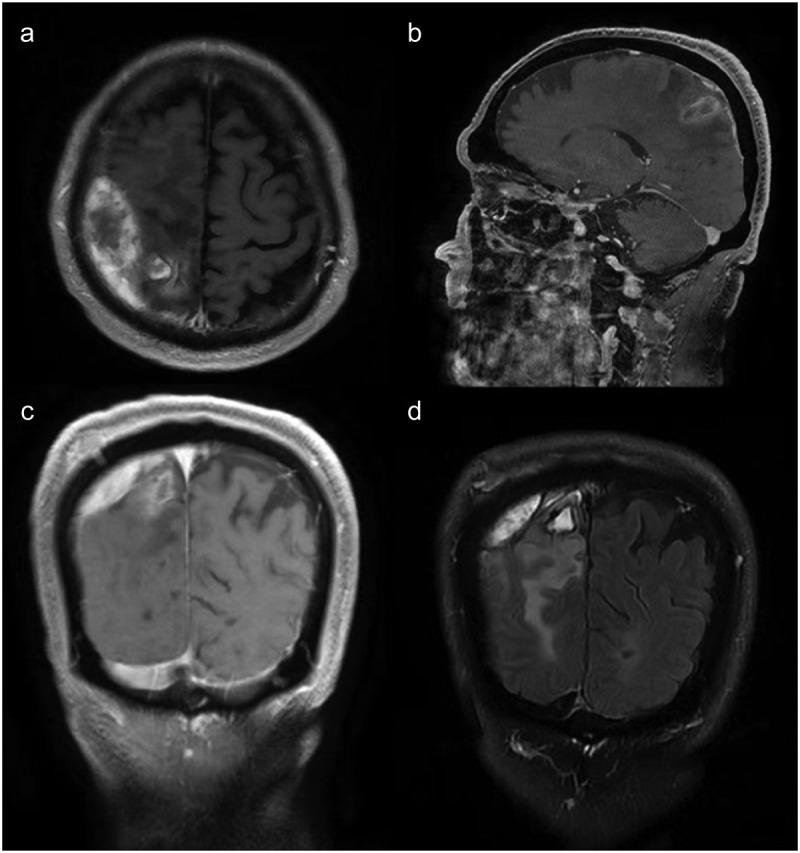

This case reports a 70-year-old male patient who developed an odontogenic brain abscess secondary to periodontal infection and underwent neurological surgery. Extract pus during surgery for the metagenomic next-generation sequencing (mNGS).

The mNGS of pus samples obtained from brain abscess aspiration identified the periodontal pathogens and . Consequently, he was referred to the department of stomatology for further examination and treatment.